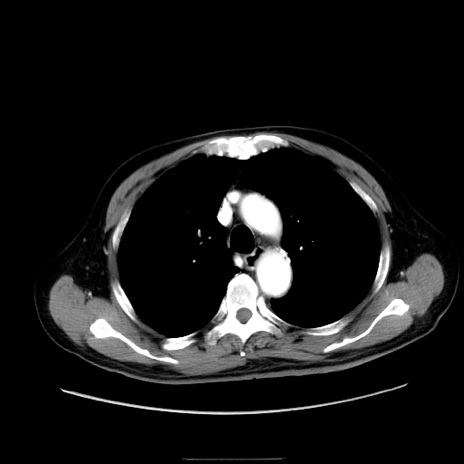

症例30(横断像)

【症例】80歳代男性

【主訴】臍周囲痛

【現病歴】約6時間前から臍下部痛が出現。次第に腹部膨隆・背部痛も生じてきたため来院。背部痛の場所は変化しない。

【身体所見】意識清明、BT 36.3℃、BP  131/87mmHg、P 87bpm、SpO2 100%(RA)、臍周囲自発痛・圧痛あり、反跳痛なし、自発痛部位に一致して板状硬あり、腹部膨隆、腸雑音減弱、CVA tenderness両側陰性。